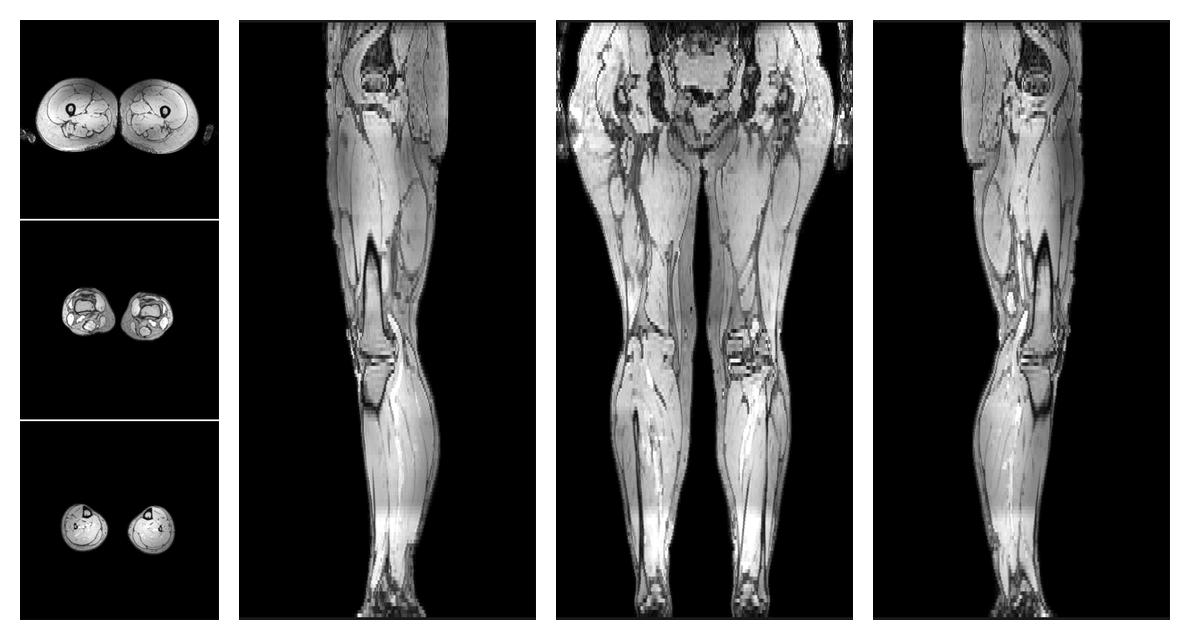

• Water only signal

The water part of the acquired multi-echo spin echo data.